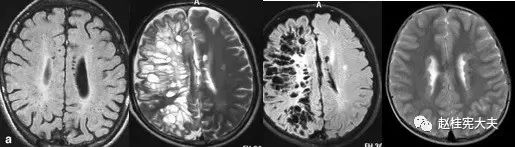

重要申明:以下每个部分会配磁共振图片,因疾病和影像之间存在同病异象、同像异病,为避免误导,图片不标注疾病,请各自鉴赏,另其中有部分图片来源于网络,有疑问可与本人联系。

I--inflammation,炎症

脱髓鞘,多发性硬化(MS)、视神经脊髓炎(NMO)、急性播散性脑脊髓炎(ADEM)、MOG相关性脱髓鞘病变、自身免疫性脑炎、CNS血管炎、神经系统结节病、Susac's Syndrome、Clippers’综合症、桥本氏脑病等。还有如急性、亚急性的放疗损伤等。

S--stroke,卒中,即血管性

各种动脉性、静脉性血管病、静脉窦血栓形成、动脉夹层致脑梗塞、脑小血管病、脑动静脉畸形、CAA等,Moya-Moya也可出现脑实质的多发病灶,易被误诊为脱髓鞘。

除此之外,还有一些解剖结构变异造成的病变,如V-R间隙扩大,灰质异位等。